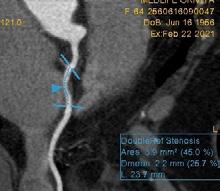

Figura 1. Pacient de 57ani cu simptomatologie acută sugestivă pentru AVC ischemic acut: CT -ul nativ nu a decelat elemente de semiologie sugestive pentru AVC ischemic acut (A), însă secvențele IRM au evidențiat o arie în hipersemnal FLAIR (B) și cu restricție de difuzie (C) localizată occipital paramedian dreapta, sugestivă pentru AVC ischemic acut (Spitalul Clinic de Urgență „Prof. N. Oblu“, Iași)

În contrast, imagistica prin rezonanță magnetică, în special secvențele de difuzie, oferă o sensibilitate superioară pentru detectarea precoce a infarctului ischemic,

fiind capabilă să identifice modificări la nivel celular la doar câteva minute după debutul simptomelor (Figura 1) (Mouridsen et al., 2020), (Nukovic et al., 2023). De asemenea, IRM este capabilă să ofere o evaluare superioară a integrității parenchimului cerebral, a viabilității țesutului și a extinderii leziunii ischemice, facilitând o caracterizare mai detaliată a AVC-ului ischemic (Cortés-Albornoz et al., 2025).